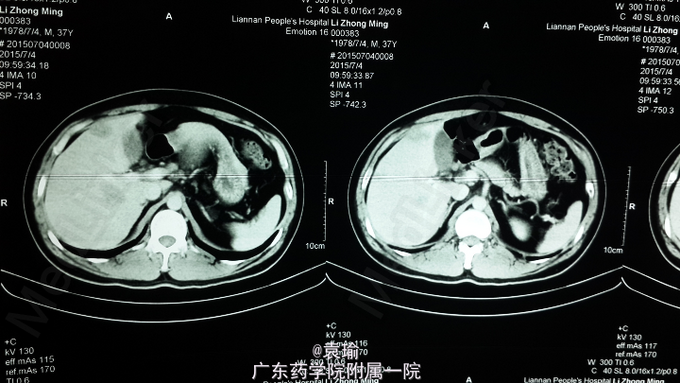

查体:T 36.5℃,P82次/分,R20次/分,BP 105/73mmhg, 巩膜轻度黄染,全身 皮肤无黄染,无贫血貌,未见肝掌、蜘蛛痣,浅表淋巴结未扪及肿大。心、肺查体无明显异常。腹平坦,腹肌软,右上腹轻压痛,无反跳痛,全腹未扪及明显包块,肝、脾肋下未扪及,墨菲氏征阴性,麦氏点无压痛,肝浊音界存在,肝肾区无叩击痛,腹部移动性浊音阴性,肠鸣音活跃。 辅助检查:多次血常规检查见嗜酸性粒细胞计数及比例增高(见附图),肝功能检查异常(见附图),超敏C反应蛋白6.200mg/L,降钙素原0.076ng/ml,余大、小便常规正常,多次大便找虫卵阴性,肾功能、凝血功能、血脂均正常,肿瘤指标(AFP、CEA、Ca-199、CA-125、CA-724、CA-153)均正常,胃镜检查示非萎缩性胃炎轻度,多点活检未见明显嗜酸性粒细胞浸润。腹部MR+MRCP:肝内多发异常信号影,考虑感染性病变,注意寄生虫感染可能,MRCP未见异常。